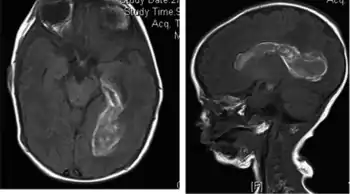

| MRI of brain showing intraventricular hemorrhage | |